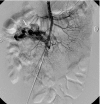

Discussion: Vascular malformations of abdominal viscera, especially the small intestine, are rare clinical manifestations in pediatric patients but are among the important causes of acute massive or chronic obscure LGI bleeding. Unless there is significant GI bleeding, patients are usually treated for anemia with obscure LGI bleeding. In the present study, selective angiography was useful in one case and CT enterogram with angiography was useful in the other case.